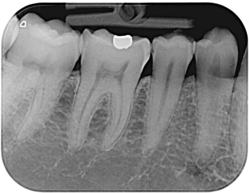

Digital Xrays

Using a small sensor placed briefly in the mouth, an x-ray image of high analysis is obtained.

This sensor functions as a miniature camera that is more sensitive to the radiation of the radiographic apparatus with respect to the normal light.